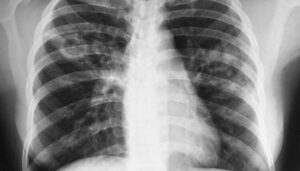

Причины, симптомы и методы лечения рака лёгких

Рак легких считается одним из самых распространенных онкологических заболеваний в мире. Ежегодно регистрируется не менее одного миллиона новых случаев этого заболевания. Согласно статистическим данным, пик заболеваемости в России приходится на возраст 55-75 лет. Аналогичная ситуация и в других странах. Статья посвящена особенностям онкологических заболеваний легких у пациентов разных возрастных групп. Дети и подростки Первичный рак …

Перелом ребер

Перелом ребер не сопровождается патологией, опасности для жизни человека нет. Но при наличии сопутствующих травм возможны осколки, поражение легких и летальный исход. Поэтому в обязательном порядке необходимо оказать пострадавшему своевременную помощь. Первая помощь при переломах ребер предусматривает соблюдение определенного алгоритма действий. Симптоматика травмы Если у человека сломаны ребра, для него будут характерны следующие ощущения: Крепитация …

Паллиативная помощь при раке легкого

При распространенном раке легких выживаемость низкая, а таргетная терапия и иммунотерапия не всегда эффективны. Пациенту остается жить не более 6 месяцев, которые он проведет в условиях сильной боли и тяжелой депрессии без необходимой помощи. Как можно освободить умирающего? Общая информация Паллиативная помощь — это особая область медицины, основной задачей которой является использование современных и традиционных …

Как происходит заражение детей туберкулезом

Туберкулез — заболевание большого социального значения, которое с каждым годом становится все более частым. Проблема инфекций особенно остро стоит у пациентов детского возраста из-за несовершенной диагностики и отсутствия знаний и опыта педиатров в области фитизиологии. Дети более подвержены туберкулезу, чем взрослые, из-за несовершенной иммунной системы. Причины инфицирования (возбудители) Туберкулез вызывают бактерии из семейства Mycobacteriaceae, которое …

Пневмония или бронхит: симптомы и признаки

Заболевания органов дыхания и сердечно-сосудистой системы играют ведущую роль в структуре соматической заболеваемости населения мира. Важность бронхита и пневмонии определяется большим количеством различных возбудителей и их частым возникновением. Хотя эти патологии различны, сходные клинические симптомы могут затруднять постановку точного диагноза. Из этой статьи вы узнаете, в чем разница между бронхитом и пневмонией и как различать …